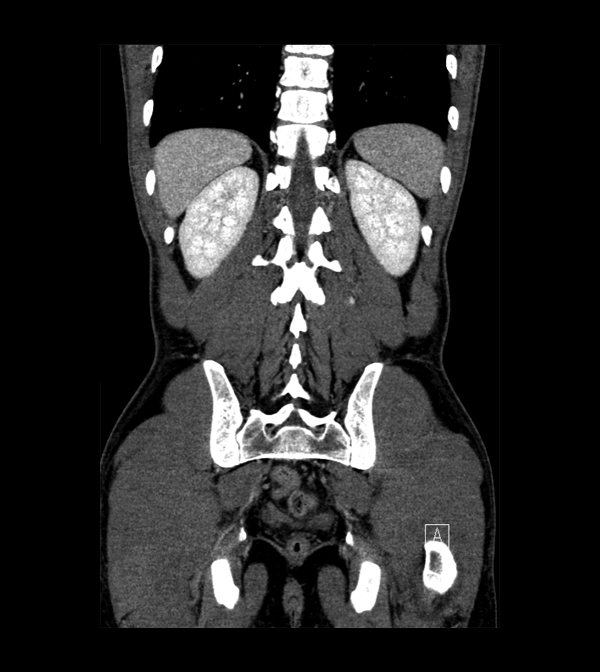

Body

Covers abdominal CT anatomy.